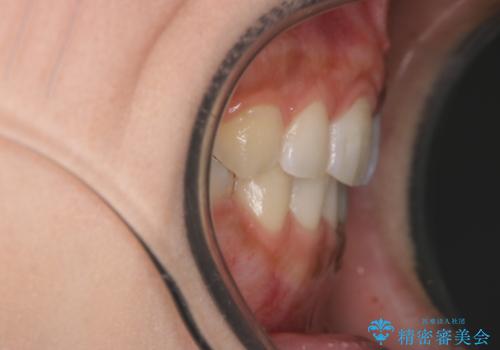

口元をさげたい ワイヤーによる抜歯矯正

- 口元が出てるのが気になるとのことで来院されました。

上下左右前から4番目の歯を抜歯して前歯を後方に下げて、口元を下げる計画としました。